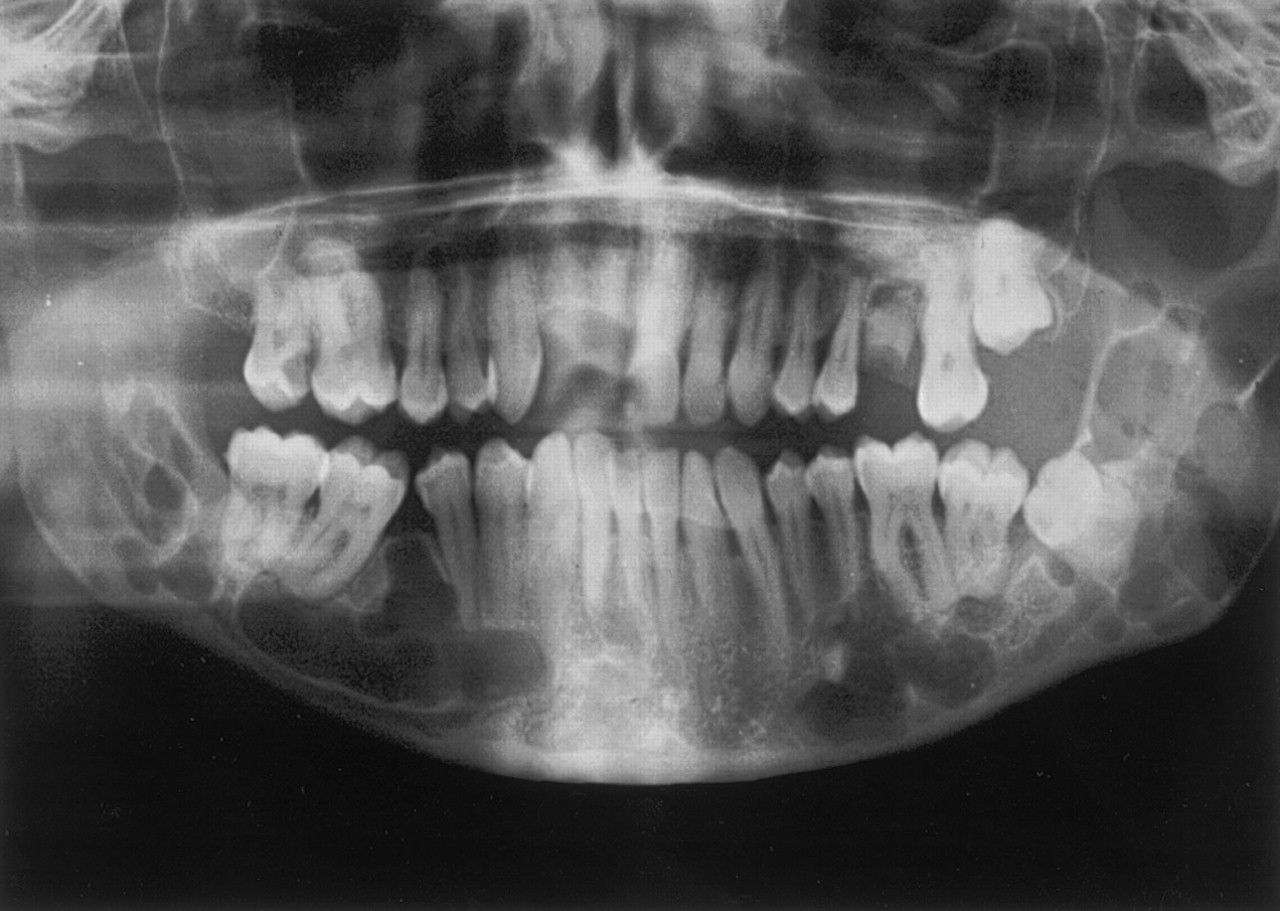

XRAY: UNILOCULAR radiolucency, well defined (sclerotic border)

Most commonly associated with 3rd molars

MOST COMMON DEVELOPMENTAL ODONTOGENIC CYST

Treatment: Enucleation of the cyst with the unerrupted tooth.